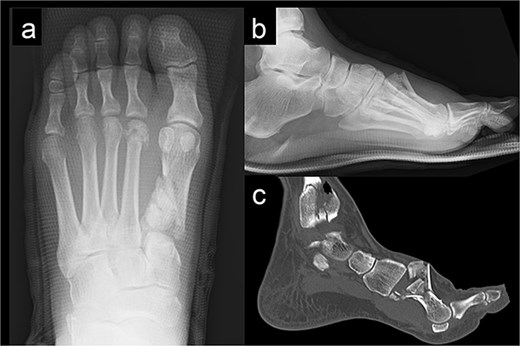

We performed surgery in two stages, owing to the poor condition of the skin. In the first stage, we performed screw fixation for the tibial pilon fracture and plate fixation for the distal fibular fracture. For the first-metatarsal fracture, half pins for external fixation were inserted into the first proximal phalanx, first metatarsal, medial cuneiform, and navicular bone. The external fixator (The Small External Fixation System, Synthes, Oberdorf, Switzerland) was stabilized with the first reduction in the metatarsal shortening deformity (Fig. 2). One week later, the second-stage surgery was performed after the swelling of soft tissues on the dorsum of the foot had improved. A longitudinal skin incision was made on the dorsum of the first metatarsal, and a fusion plate (Variable Angle LCP Forefoot/Midfoot system, Synthes) was placed on the dorsal aspect of the first metatarsal and the medial cuneiform. Three screws were inserted into the medial cuneiform, and four screws were inserted into the distal end of the first metatarsal. Postoperative radiography and CT images are shown in Fig. 3.

Radiography (a, b) and computed tomography (c) images immediately after the second surgery.